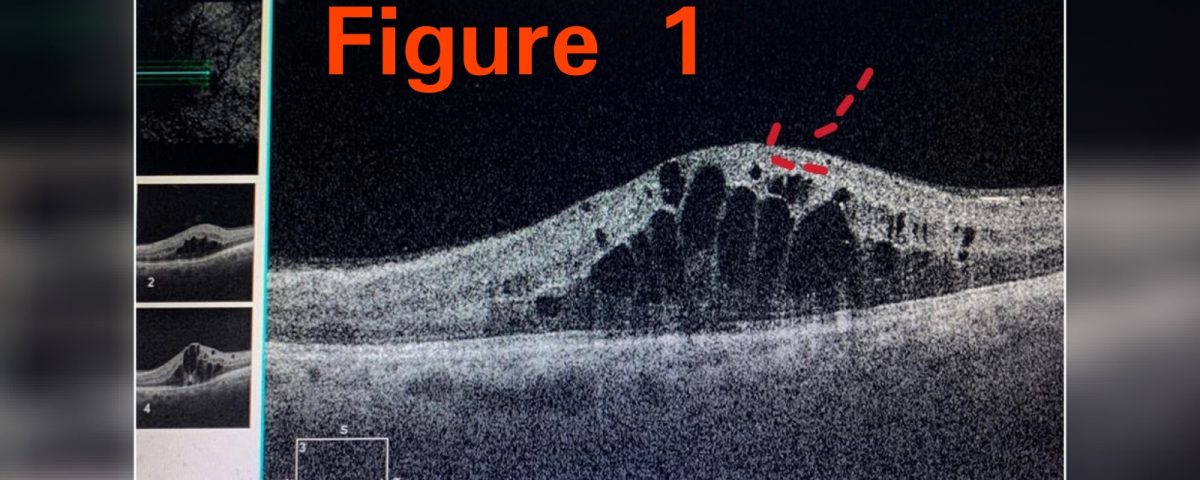

A 40 year old DIABETIC male came with complain of decrease in vision in left eye. On detailed eye examination, it was found that patient had macular edema ( collection of fluid in central part of retina). (Figures 1 and 2 - Red arrows). At that time patients vision in left eye was 6/24 (3 lines on vision chart). After 2 Anti - vegf injections inside the eye, patients vision improved to 6/6 (all the lines on vision chart). (Figure 3).